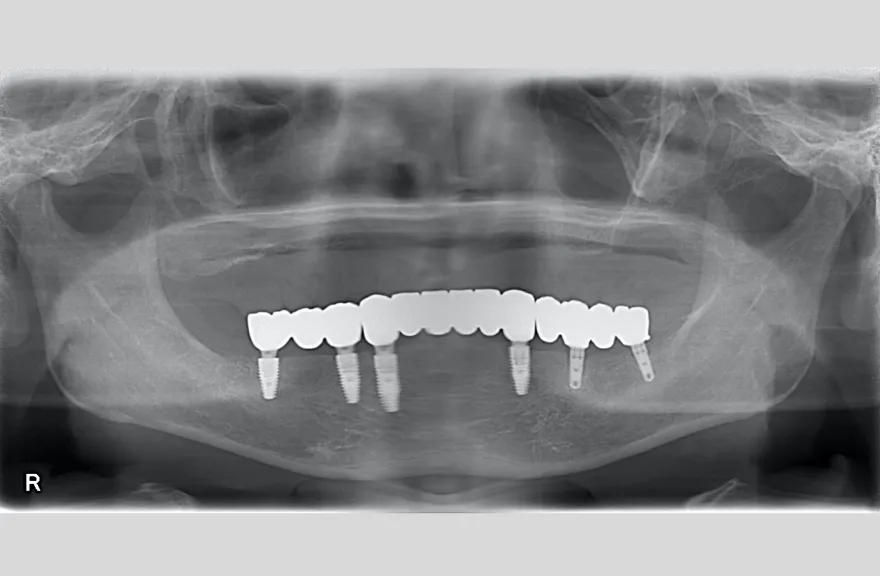

レントゲンをよく見るとお分かりいただけるかと思いますが右下の奥歯のインプラント(レントゲンでは左右逆にうつるので、左下)が既にインプラント周囲炎になっていました。

本当に治療をやり切ってしまうなら、右下の奥2本のインプラントを抜去、新しいインプラントフィクスチャーを埋入すべき症例でした。

しかし、患者さんとの話し合いで、「まだ使えるインプラントは置いておこう」ということになり、右下のインプラントは置いたまま治療を行っています。今後の人生の中で腫れたり痛む可能性があることは重々ご承知いただいております。

複数のインプラントフィクスチャーの埋入においては埋入位置がずれると後々のクラウン製作に難が生じます。そのリスクを最低限にするため、ガイデッドサージェリーを行っております。